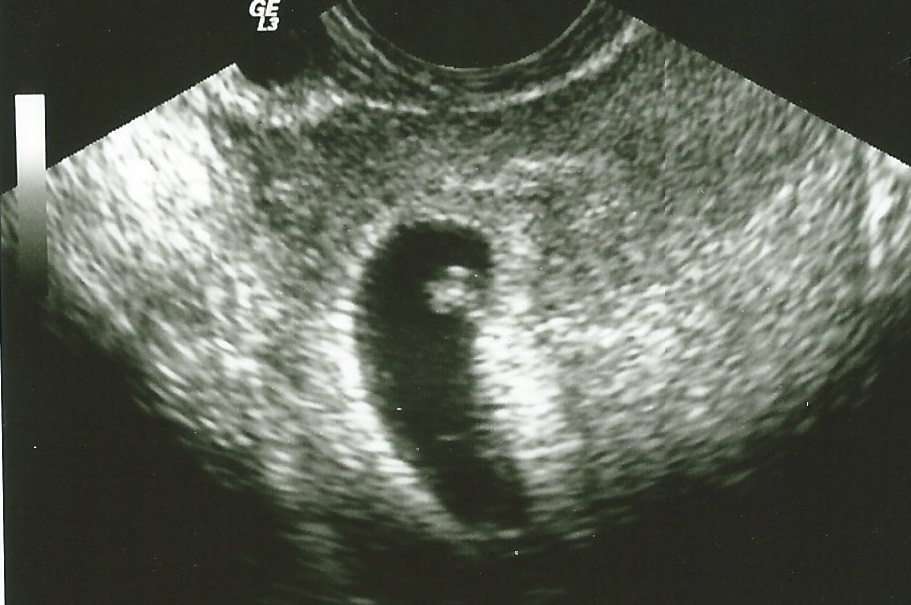

So since I introduced myself I haven't been real active so I apologize for that. I had some pretty bad cramping today and it was stronger than I've had so my DH called the RE. They had us come in today for an ultrasound and we were able to see everything is just fine. I was measuring a few days behind but we saw and heard the heartbeat it was at 115. We didn't get to see our doctor, we saw another of the docs in the practice. He said to keep our ultrasound appt for Tuesday with our doctor so I get to see our little bean again in a few days. I am breathing a bit easier now but know we aren't out of the woods yet. Below is the picture.

Me 29 DH 30 Unexplained IF TTC since wedding May 2012. IUI #1 11/5/13-BFN. IUI #2 12/5/13-BFN. IUI #3-12/30/14. All three with Femara CD 3-7 and Ovidrel trigger. +HPT 1/13/14 First +ever!!! Beta #1 195 Beta #2 1/15-533. Ultrasound on 2/4 showed one bean. EDD 9/22/14. Team Green turned Team Blue-Baby Conner arrived on 9/19/14.